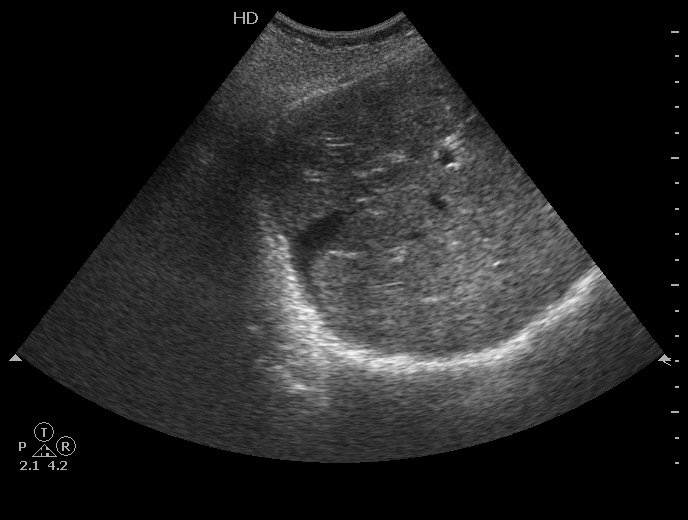

Добавлю еще пару случаев

#2

#3

Краевой разрыв с гемоперитонеумом (вне поля сканирования)